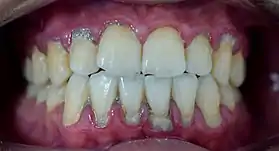

Heavy staining and calculus deposits exhibited on the lingual surface of the mandibular anterior teeth, along the gumline